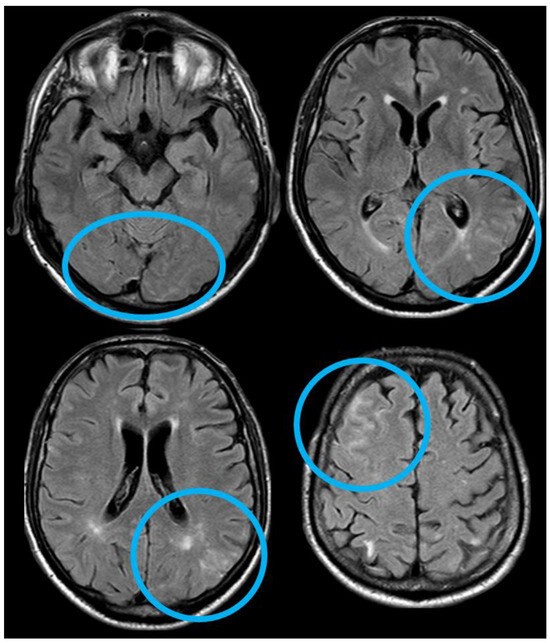

2. December 2013: Sulcal SAH and TFNEs

3. May 2014: CAA-Related Inflammation

4. December 2015: Ischemic Stroke

5. February 2017: First Recurrent CAA-Related Inflammation

6. December 2017: Recurrent SAH

7. April 2018: Second Recurrent CAA-Related Inflammation

8. April 2018: Third Recurrent CAA-Related Inflammation